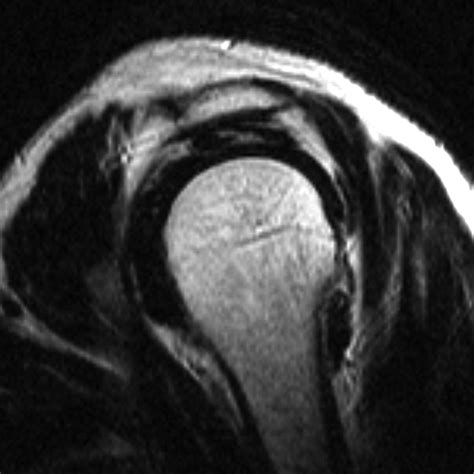

Diagnosing Acromion Types

Diagnosing the type of acromion typically involves a combination of physical examination and imaging studies. Radiographs (X-rays) are commonly used to visualize the shape of the acromion. Magnetic Resonance Imaging (MRI) and Computed Tomography (CT) scans can provide more detailed images of the shoulder joint and surrounding structures, aiding in the diagnosis of acromion types and associated conditions.